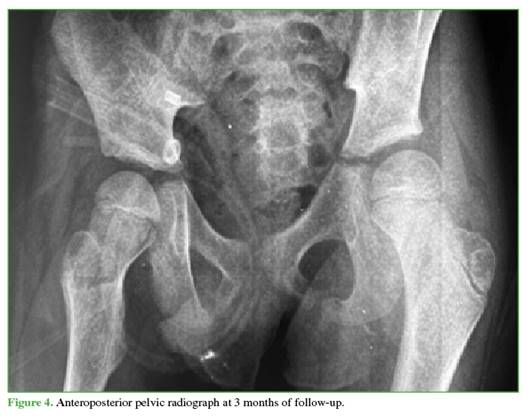

Follow-up radiographs at 3 (Figure 4) and 6 months (Figure 5) showed no evidence of AVN, and other musculo-skeletal complications associated with traumatic dislocation were also ruled out.

Reported complications include coxa magna, sciatic nerve palsy, paresthesias, and AVN of the femoral head.10 In patients under 18 years of age, the incidence after isolated dislocation ranges from 3% to 15%,17 and is higher if reduction is delayed.18 Therefore, imaging follow-up is essential. Although there is no consensus on ideal timing, in this case, check-ups were performed at 3 and 6 months, and no radiographic evidence of AVN was detected.

Follow-up radiographs showed no signs suggestive of AVN (sclerosis, collapse, cysts, joint-space narrowing, etc.).22 These findings may take 2 to 6 months to become visible on radiographs,20 so the follow-up schedule was appropriate.

Despite the absence of radiological signs of AVN up to 6 months, continued imaging follow-up is necessary to detect potential development of AVN, which may take up to 2 years to manifest.25